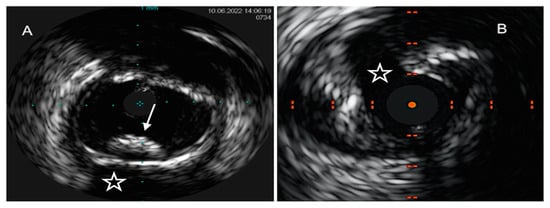

IVUS was the first IVI technique introduced into the clinical setting more than thirty years ago. The IVUS system consists of a sound probe located at the distal part of a dedicated catheter, emitting high-frequency sound waves from 20 to 60 MHz. Through the densitometric quantitative analysis of ultrasound signals, IVUS offers a real-time monochrome cross-sectional image of the full circumference of the coronary artery wall and atherosclerotic plaques. A major limitation of IVUS lies in the insufficient discrimination between lipidic and fibrolipidic plaques and in the flawed evaluation of tissues with overhanging superficial macrocalcification [38][54]. Virtual-histology IVUS (VH-IVUS), by means of radiofrequency ultrasound backscatter data and a color-coded map, was able to overcome these pitfalls, leading to a classification of coronary atherosclerotic plaques into four phenotypes with high diagnostic accuracy as compared to matched histopathological results: calcified and fibrous plaques are recognized as hyperechoic and homogenous structures, marked in white and green, respectively, on the color-coded map, while lipidic and mixed/fibro-fatty plaques were labeled as low-density regions, with a red and yellow appearance, respectively [39][55] (Figure 1).

Figure 1. IVUS images of coronary plaque phenotype. (A) Example of a calcific plaque, depicted as a bright leading circumferential structure ((A), white arrow) with deeper shadowing ((A), white star). (B) Example of predominantly fibro-fatty plaque, depicted as a structure showing less echogenicity than the surrounding adventitia with a spotty calcification ((B), white arrow), characterized by a focal hyperechoic signal and deeper shadowing.